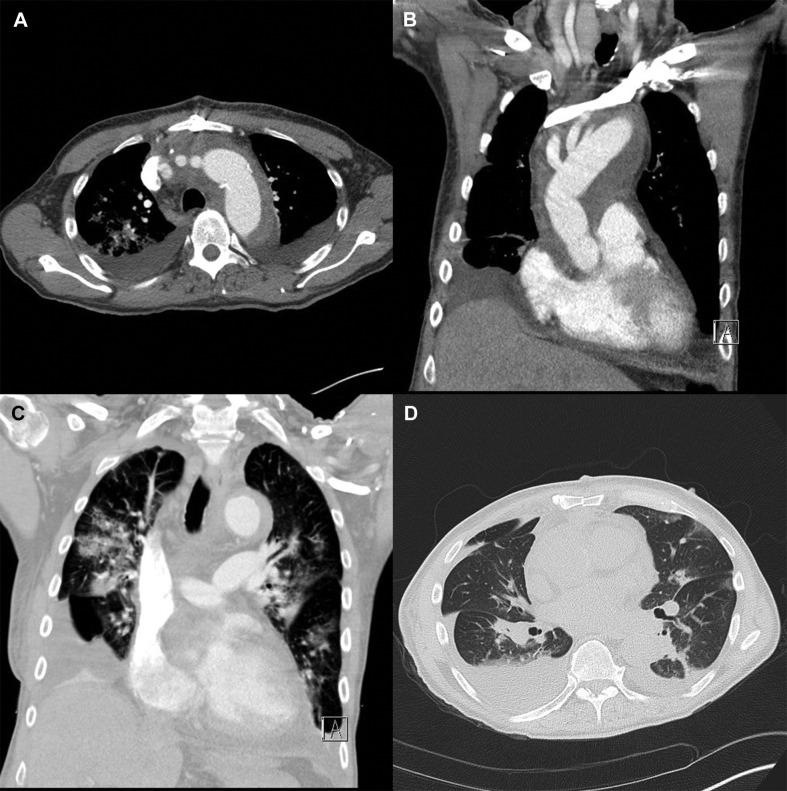

A patient underwent surgery for acute type A aortic dissection. Testing for SARS-CoV-2 was positive. The postoperative course was complicated by a mixed viral and bacterial pneumonia with bilateral infiltration, treated with antibiotics and hydroxychloroquine, without any need for reintubation. The patient recovered and finally could be discharged. This report shows the feasibility for surgical treatment of acute aortic disease in patients with COVID-19.

一位患者因急性 A 型主动脉夹层接受了手术。SARS-CoV-2 检测呈阳性。术后患者并发混合性病毒和细菌性肺炎,出现双侧浸润,使用抗生素和羟氯喹治疗,无需再次插管。患者康复,最终出院。本报告表明 COVID-19 患者接受急性主动脉疾病手术治疗是可行的。